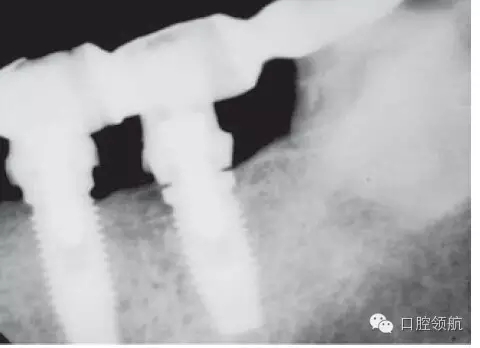

另外一個方面,深的袖口將妨礙修復體完全就位(圖9.26)。通??梢酝ㄟ^放射學檢查,確認修復部件的就位情況,包括種植體與基臺的連接部分。即使是內(nèi)連接,轉(zhuǎn)移體或者其他修復部件也會因深袖口而不能就位。以下技術可以用于解決這些問題:可以在局部麻醉下,插入喇叭狀或者外展的基臺,以非手術的方式擴大袖口(圖9.27 a,b),然后再通過放射學檢查確定部件的完全就位。組織會受壓發(fā)白,15分鐘后,軟組織將會擴張,以允許理想修復部件的就位,這樣治療將得以繼續(xù)。有時,需要在鄰面做兩個小切口,以緩解袖口軟組織張力(圖9.28 a,b)。通常不需要縫合。一旦袖口組織塑形完成,可運用最佳塑形的臨時(圖9.29)或最終部件(圖9.30),來維持理想的軟組織外形。

圖9.26 放射學影像顯示,在外六角連接的種植體上,基臺沒有完全就位。